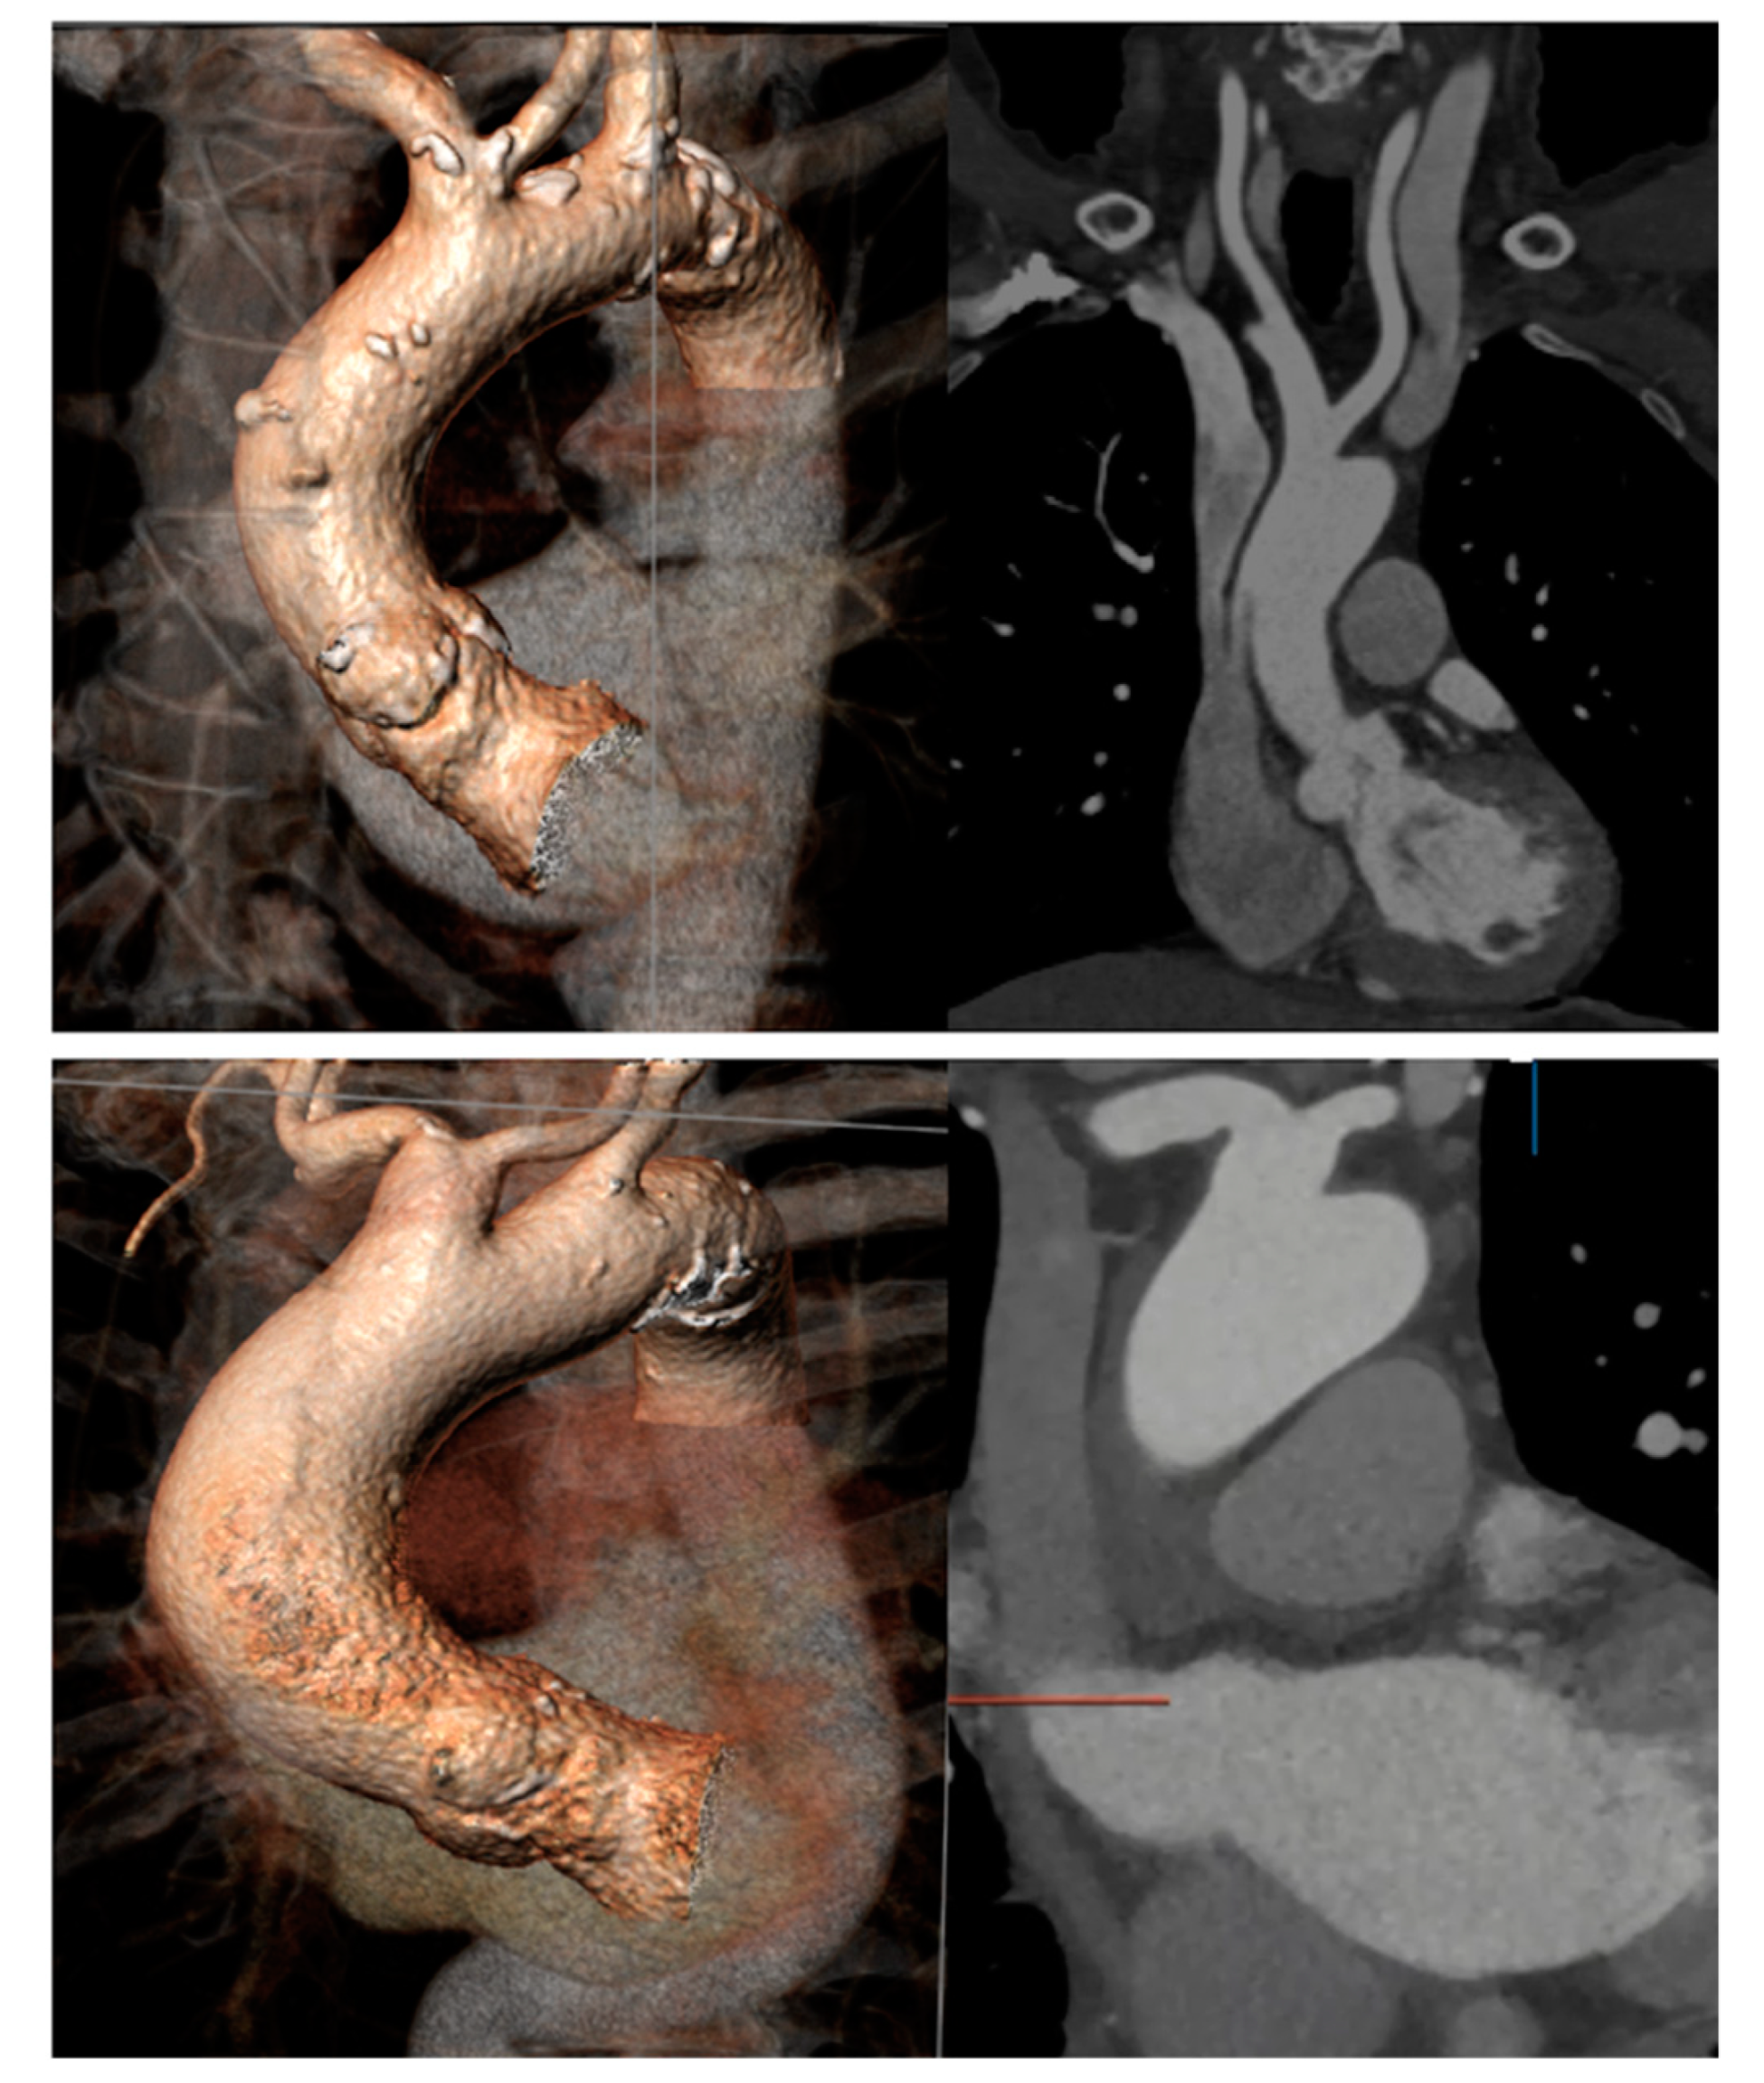

- Marrocco-Trischitta, M.M.; Alaidroos, M.; Romarowski, R.M.; Secchi, F.; Righini, P.; Glauber, M.; Nano, G. Geometric Pattern of Proximal Landing Zones for Thoracic Endovascular Aortic Repair in the Bovine Arch Variant. Eur. J. Vasc. Endovasc. Surg. 2020, 59, 808–816. [Google Scholar] [CrossRef] [PubMed]

- Marrocco-Trischitta, M.M.; Alaidroos, M.; Romarowski, R.; Milani, V.; Ambrogi, F.; Secchi, F.; Glauber, M.; Nano, G. Aortic arch variant with a common origin of the innominate and left carotid artery as a determinant of thoracic aortic disease: A systematic review and meta-analysis. Eur. J. Cardio-Thoracic Surg. 2019, 57, 422–427. [Google Scholar] [CrossRef] [PubMed]